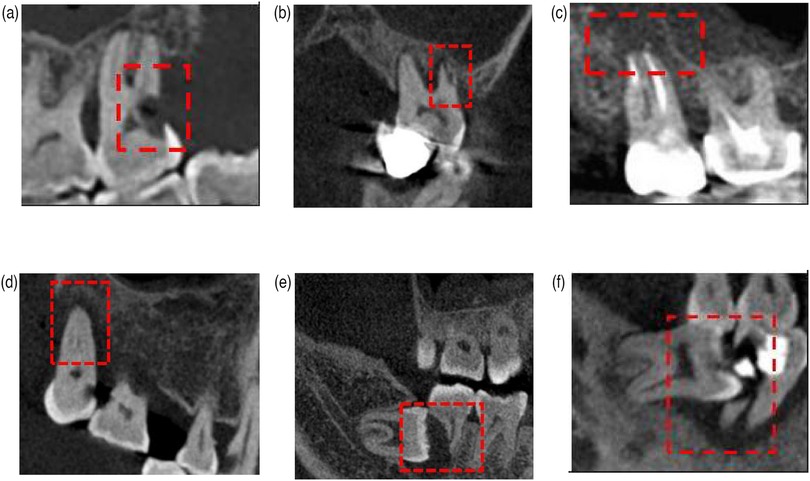

Objective: The reasons for second molar extraction include endodontics, periodontal disease, and impacted third molars. This retrospective study analyzed medical records and image examinations of patients who underwent second molar extraction to clarify the proportional distribution of different causes. Materials and Methods: Medical records and imaging data of patients who underwent second molar extraction between January 1, 2020 and December 31, 2022 were systematically collected. Two senior dentists analyzed and recorded patient demographics, clinical diagnoses, and extraction causes. Inter-rater consistency was verified using Kappa testing. Results: A total of 1,818 valid cases were included with a mean age of 52.9 years (male: 864 cases; female: 954 cases). Endodontic factors accounted for 1,045 second molar extractions (57.43%) and periodontal factors contributed to 588 extractions (32.40%), both showing significant age-related correlations (p<0.05). Impacted third molar factors led to 185 extractions (10.01%) with no significant age-dependent association (p>0.05). Impacted third molars contributed to 13.97% of mandibular second molar extractions, while only 5.73% to maxillary second molar extractions. Conclusions: The main reasons for extracting second molars were endodontic factors, followed by periodontal factors, and impacted third molars. Advanced age was significantly associated with increased extraction risks attributable to both endodontic and periodontal disease. Impacted third molar-related factors accounted for a larger proportion in cases of mandibular second molar extractions.